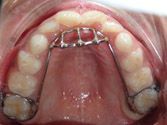

Other types of orthodontic appliances may also be used during the course of treatment. Some of these appliances are removable and can be taken in and out of the mouth, while others will be attached to the teeth until they are no longer needed.

Depending upon the specific needs of the case, these appliances may be used to accomplish a number of things including:

- Widening the jaws to make sufficient space for permanent teeth

- Influencing jaw growth

- The reduction of deep overbites

- Allowing the correction of teeth in crossbite

- Maintaining the space for a permanent tooth when a baby tooth has been prematurely lost

- Minor tooth movement

- Helping to control harmful oral habits